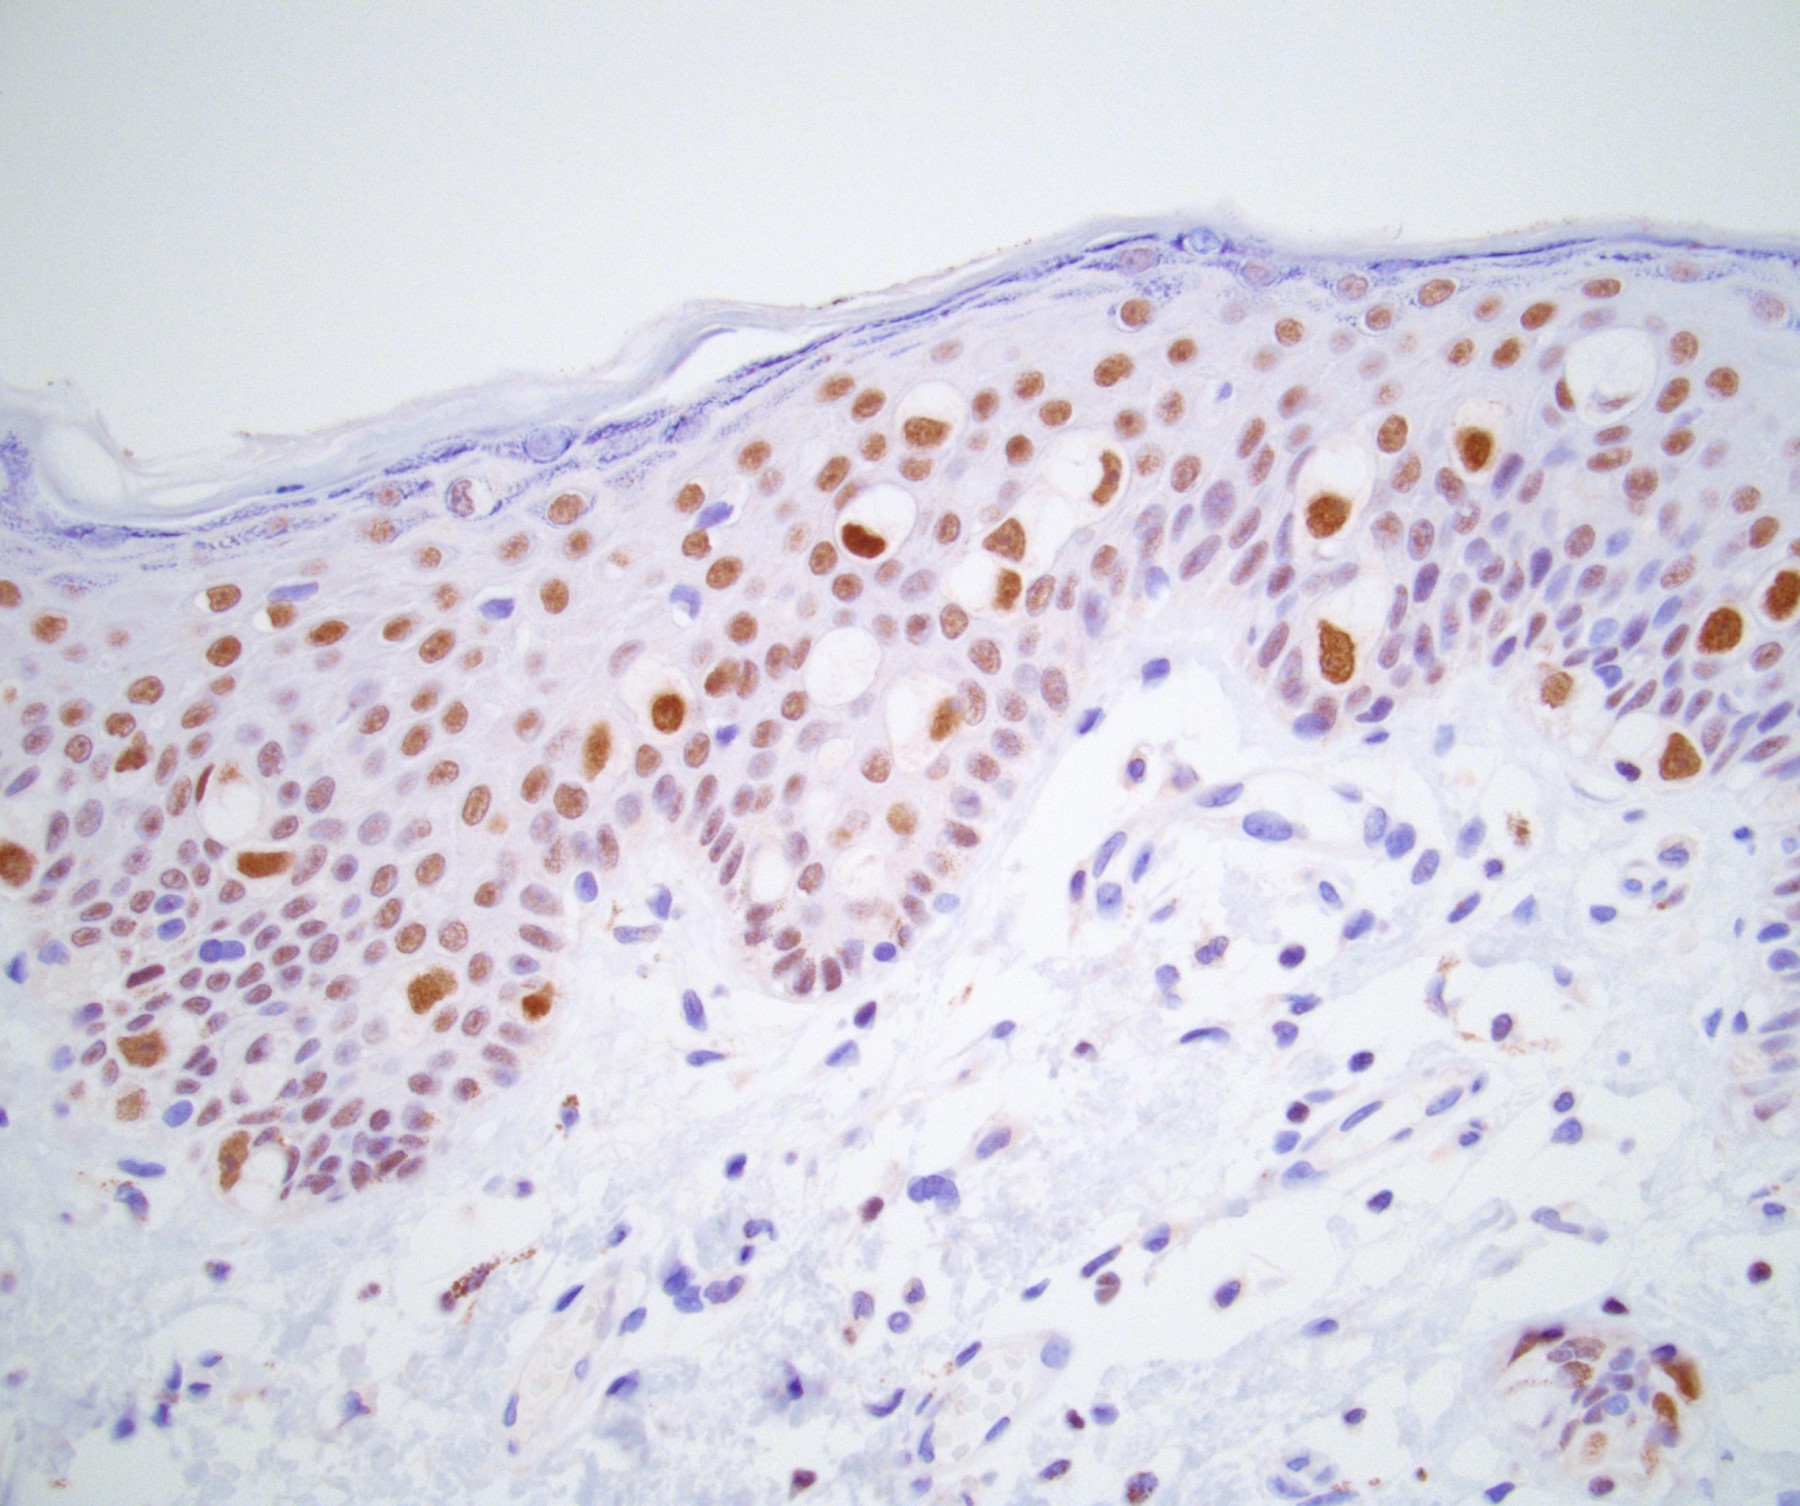

Pathology Outlines Extramammary Paget disease

Pathology Outlines Extramammary Paget disease Extramammary Paget's Disease Scrotum Icd 10 extramammary paget's disease (empd) is a rare cutaneous malignant disease. paget disease of the penis and scrotum is a rare, intraepidermal adenocarcinoma; Due to its rarity, there is a. extramammary paget disease (empd) is a rare. It arises as a primary. extramammary paget disease (empd) is defined as intraepidermal adenocarcinoma. Extramammary Paget's Disease Scrotum Icd 10.

Pathology Outlines Extramammary Paget disease Extramammary Paget's Disease Scrotum Icd 10 extramammary paget disease (empd) is a rare. extramammary paget's disease (empd) is a rare cutaneous malignant disease. extramammary paget disease (empd) is defined as intraepidermal adenocarcinoma. It arises as a primary. Due to its rarity, there is a. paget disease of the penis and scrotum is a rare, intraepidermal adenocarcinoma; Extramammary Paget's Disease Scrotum Icd 10.

Pathology Outlines Extramammary Paget disease Extramammary Paget's Disease Scrotum Icd 10 paget disease of the penis and scrotum is a rare, intraepidermal adenocarcinoma; It arises as a primary. extramammary paget disease (empd) is a rare. extramammary paget disease (empd) is defined as intraepidermal adenocarcinoma. extramammary paget's disease (empd) is a rare cutaneous malignant disease. Due to its rarity, there is a. Extramammary Paget's Disease Scrotum Icd 10.